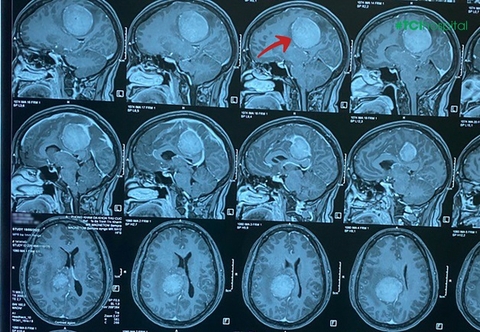

Căn bệnh gây tổn thương ở não, di chứng thần kinh, dễ mắc vào mùa hè